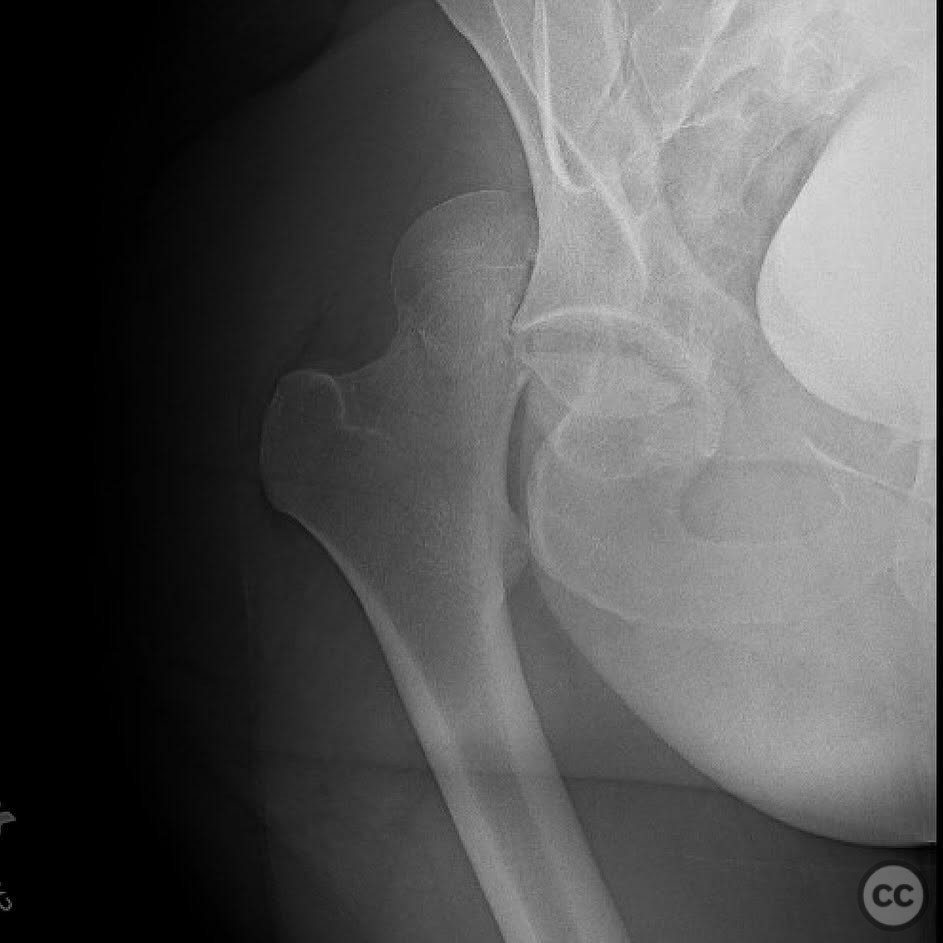

Pipkin IV Femoral Head Fracture with Ace...

Seattle, United States

Femur - AO/OTA 3x

Pipkin IV Femoral Head Fracture Dislocat...

Pipkin IV Femoral Head Fracture with Fem...

Pipkin Type III Femoral Head and Neck Fr...

Pipkin 2 + cranial peripheral acetabular...